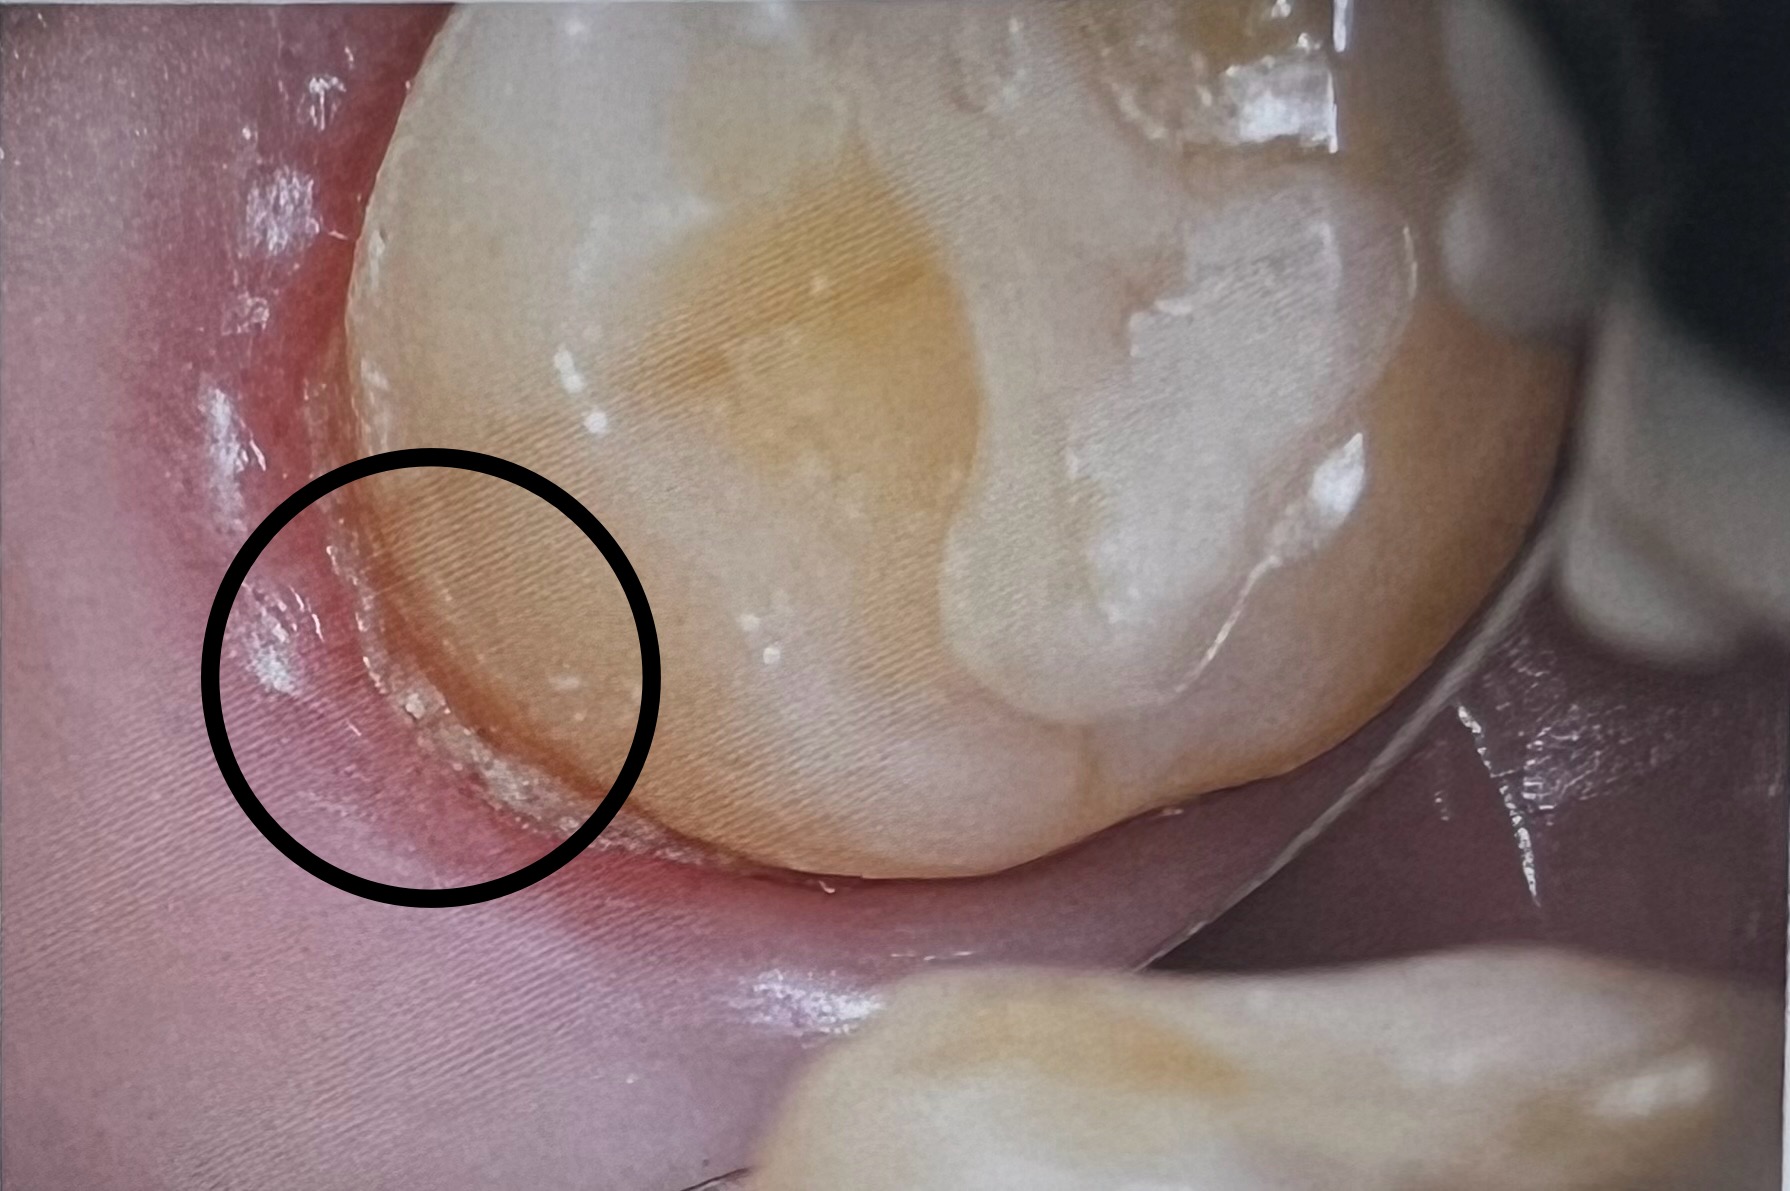

これは縁下歯石です。

超音波スケーラーを使って歯石を除去しています。

歯石を綺麗に除去できました✨

このようにマイクロスコープでは肉眼では見えづらい縁下歯石も目で見て確認しながら除去することができます‼️✨

下の写真は右下7番目の内側の写真です。よく見ていただくと黄色い汚れがべったりと付着しています。これは昨日や今日でついた汚れではなく数日汚れが重なってできた成熟したプラークになっています。

下の段の写真は細い器具で歯肉溝を広げて確認をしたものです。歯肉溝の中には汚れが石灰化した塊が付着しています。

これは、歯肉の溝にできる縁下歯石というものです。